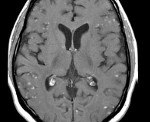

• МРТ спинного мозга и головного мозга. МРТ с контрастом определяется как утолщение мозговых оболочек, симптомы гидроцефалии (желудочковая асимметрия, расширение первичных резервуаров), полиморфные гранулемы с четкими контурами, периорбитальный отек и хорошее накопление контраста.